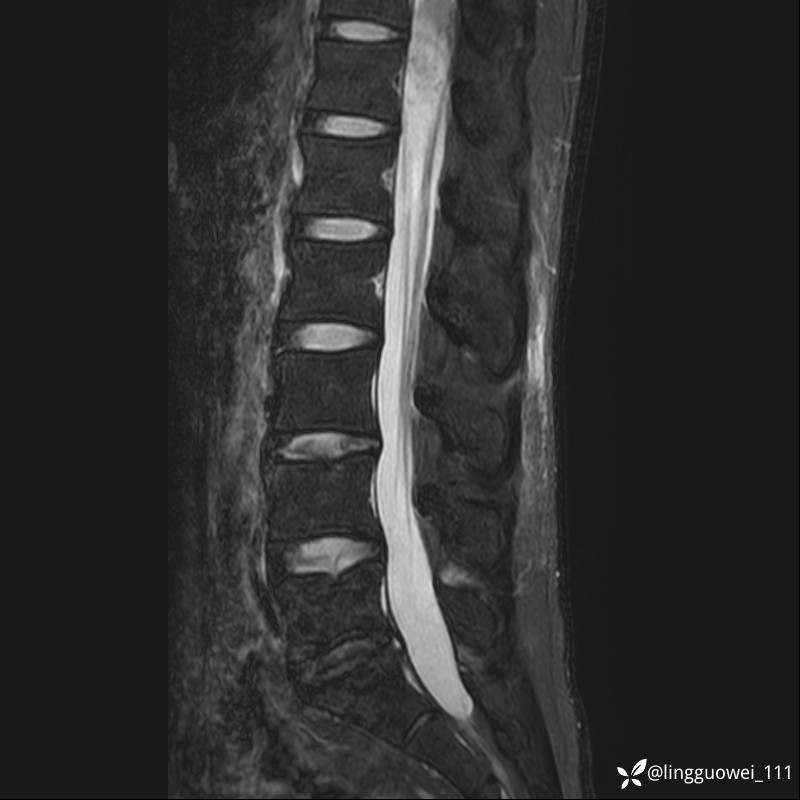

男,38岁,反复腰痛伴双腹股沟区痹痛半年,加重1月。

腰椎MR,注意脊髓异常信号,与伪影鉴别,一不小心就会漏诊

T2WI T2WI+FS